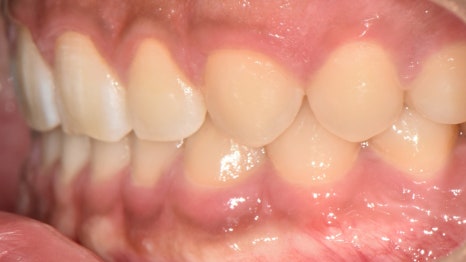

앞니는 양 옆으로 벌어진 형태였으며

양쪽 절단연이 비대칭적인

모습을 갖고 있네요.

어금니 뒤쪽은 배열에서 벗어나

삐뚤어져 있는 총생을 갖고 있었습니다.

이를 크라우딩(crowding)이라 부릅니다.

맨 뒤에있는 어금니가 올바른 맞물림이 아니라

바깥 쪽으로 뻐드러져 교합이 되지 않고 있었는데요.

구치부 교합도 훨씬 긴밀해졌으며

톱니바퀴와 같이 잘 물리고 있는 모습입니다.